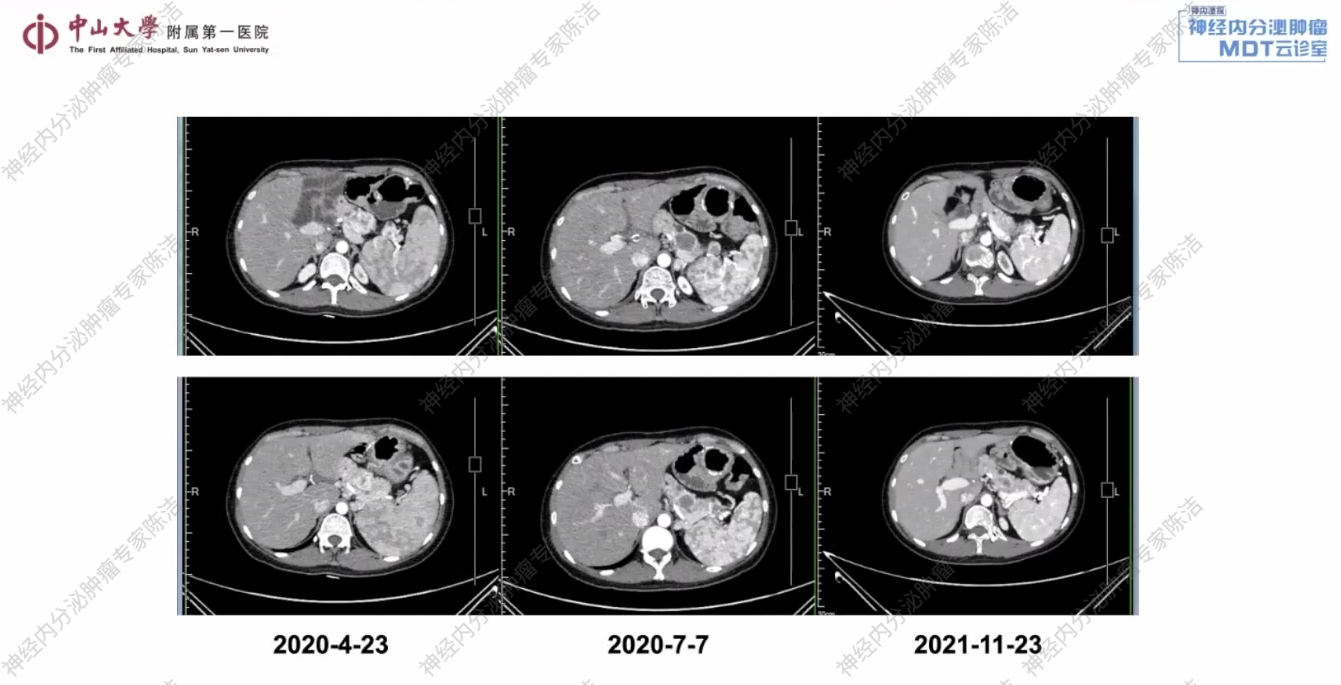

2020年7月7日(治疗约3个月后):复查CT示,胰腺病灶及转移淋巴结均较前明显缩小,疗效评估为部分缓解(PR)。

2021年11月23日(治疗约1年半后):复查CT示,病灶进一步缩小,疗效评估为PR。

放射诊断科汤伟教授:该患者胰腺体尾部及脾门区可见多个富血供占位。此外,在右侧结肠旁沟及腹膜后区域,红箭头所标示的小结节考虑为转移性淋巴结。综合判断,此为多发性胰腺NET伴腹膜后及结肠旁沟淋巴结转移。舒尼替尼治疗前后CT影像清晰地展示了肿瘤的演变过程。基线时可见胰腺体尾部的多发富血供病灶,以及腹膜后和肠系膜的转移结节。经过舒尼替尼治疗后,无论是原发灶还是转移灶,都出现了显著且持续的缩小,在影像学上达到了非常好的PR,证明了治疗的有效性。

其次,在治疗决策上,VHL基因是肿瘤血管生成通路中的一个核心抑癌基因,VHL相关肿瘤通常血供非常丰富。因此,对于此类患者,抗血管生成的靶向药物(如TKI类)是首选治疗方案。从影像学上可以看到,患者经舒尼替尼治疗后肿瘤达到PR,生活质量也得到了保障。